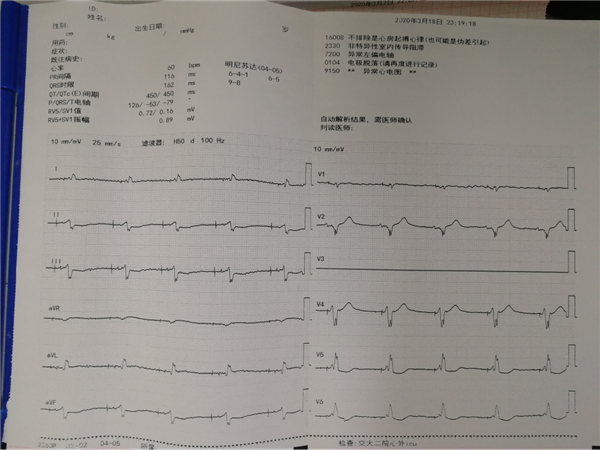

患者男,47岁,因“气短3年余,加重伴反复晕厥1天”之主诉入院。患者3年前曾因三度房室传导阻滞植入双腔起搏器,后出现反复心衰、反复室速,心脏彩超提示全心增大EF值0.23,心电图提示心房心室起搏心律,QRS210ms(见下图),曾辗转北京多家医院。最后在郑强荪教授带领的团队精心治疗下,当患者心功能相对稳定时,为患者全麻下实施CRTD植入。

团队术前缜密讨论,充分考虑多个结局,多种策略。手术由郑强荪主任,韩振华副主任,薛嘉虹副教授,王新宏副教授及导管室护士王军、杨宏斌共同完成。团队先为患者行左心室电极植入冠状静脉窦的经典CRTD,但患者冠状静脉窦分支条件较差,左侧后支迂曲盘旋,给操作带来极大的困难,经多次尝试左室电极仍不能植入成功,郑强荪主任、韩振华副主任带领的团队迅速改变策略,与时俱进,决定行左束支区域起搏。另外患者在拔除原右室电极时又因电极与上腔静脉入口处粘连拔除困难,再次为手术带来障碍,最终经团队6小时的不懈努力,手术顺利完成。术后心电图QRS波群由原来的210ms缩窄为160ms,患者心功能明显改善。

术前心电图

术后心电图